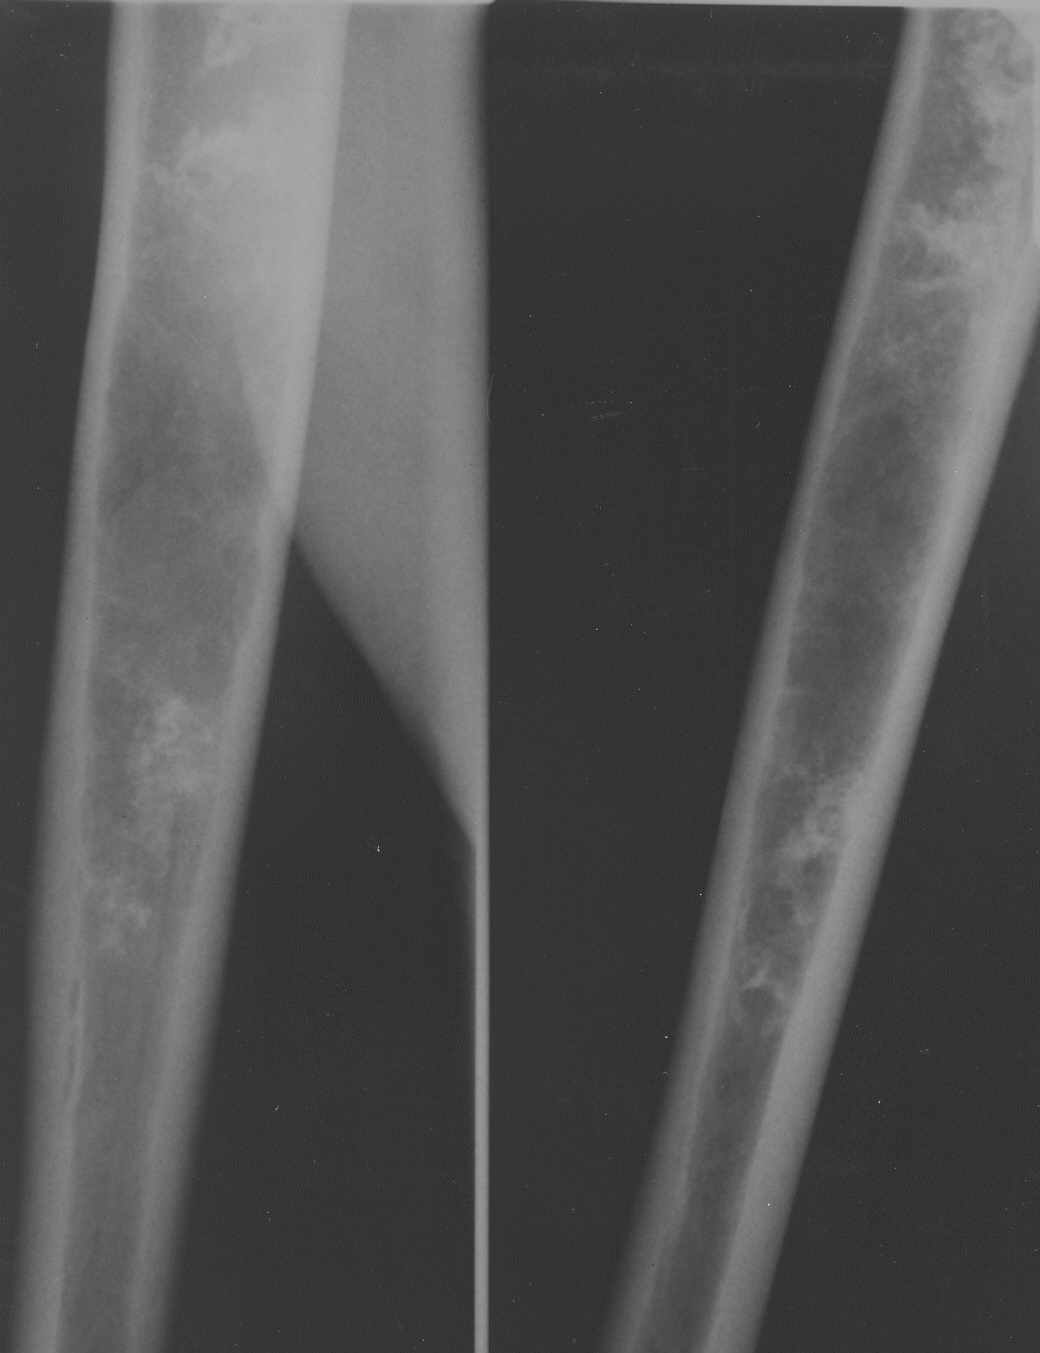

На снимках картина похожа на ENCHONDROMA

Если пациент бессимптомный - только наблюдение. Если пациент симптоматичный - стандртный протокол обследования - как при подозрении на chondrosarcoma.

Уважаемый Лев, изначально была мысль насчет опухоли хрящевого генеза, но смущает факт большой множественности очагов затемнения. К тому же, очень скудная клиническая симптоматика. Травм не было. Боли возникли внезапно несколько месяцев назад, только при движениях.

Мноэжественные очаги не исключают хрящевую опухоль.Ядумаю что надо сделать обследование - начать с BONE SCAN и анализов крови - cbc,esr,crp, alk.phosph

Недавно выполнял биопсию по поводу аналогичных очагов в бедренной кости, подозревали оссифицирующую энхондрому, оказалось - участки некроза с

оссификацией (у пациентки в анамнезе лимфогранулематоз и 18 курсов ПХТ).

Советую сделать биопсию, чтобу не гадать на кофейной гуще.